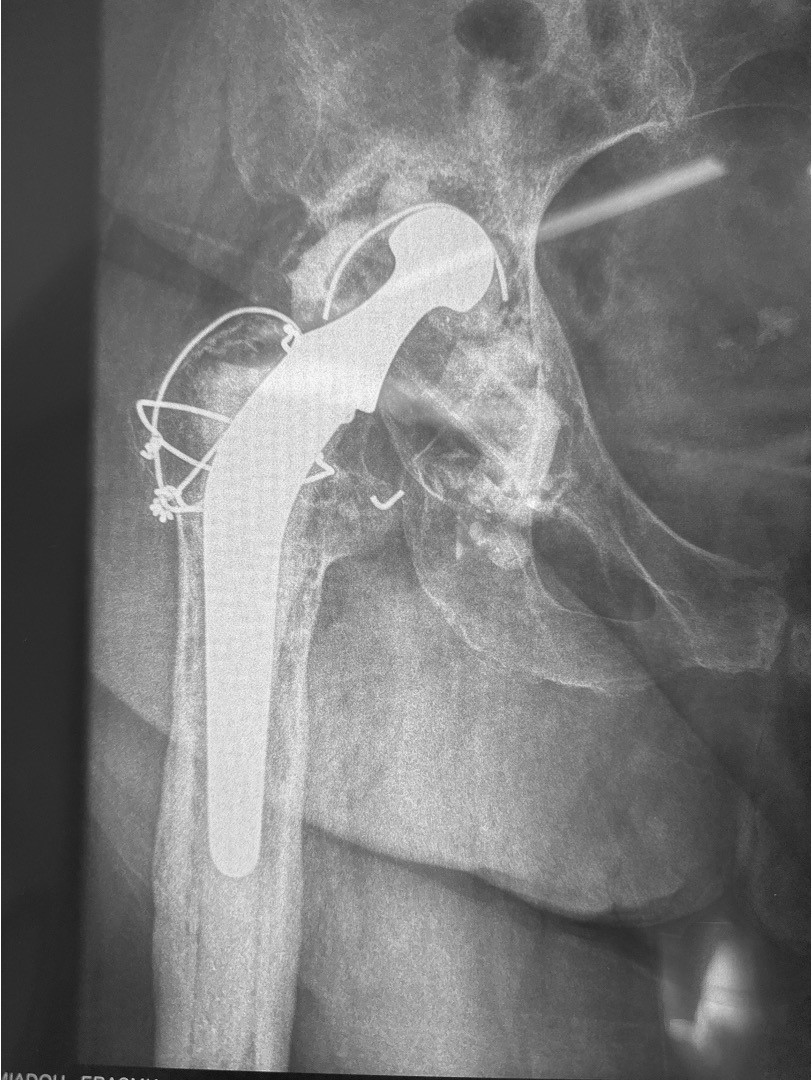

Πρόκειται για επεμβάσεις αναθεώρησης/revision των αρθροπλαστικών με τις οποίες γίνεται αφαίρεση μέρους ή όλων των αρχικών προθέσεων και αντικατάσταση με καινούργιες προθέσεις.

Κάθε περίπτωση έχει ιδιαιτερότητες που σχετίζονται με το είδος της αρθροπλαστικής που πρέπει να αναθεωρηθεί, με τον τρόπο που θα αφαιρεθούν οι παλιές προθέσεις, με την τεχνική κάλυψης των οστικών ελλειμάτων που συνήθως υπάρχουν στην περιοχή, με τον τρόπο που πρέπει να στερεωθούν τα καινούργια υλικά, με τον χειρισμό των μαλακών μορίων κ.α.

Στις περισσότερες περιπτώσεις η επέμβαση αναθεώρησης των αρθροπλαστικών δεν έχει καμία σχέση με τις τεχνικές και τα υλικά που χρησιμοποιούνται στις αρχικές αρθροπλαστικές.

Η απαραίτητη εμπειρία της χειρουργικής ομάδας που χειρίζεται αυτές τις δύσκολες περιπτώσεις πρέπει να συνδυάζεται με την χρήση σύγχρονων υλικών.

Η χρήση όμως των σύγχρονων τεχνικών και προηγμένων υλικών επιτρέπουν συνήθως μετεγχειρητικά την γρήγορη και ασφαλή κινητοποίηση.